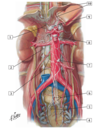

1

1 - superior mesenteric artery

2

2 - middle colic artery

3

3 - straight arteries (arteriae rectae)

4

4 - marginal artery

5

5 - right colic artery

6

6 - ileocolic artery (colic branch, ileal branch)

7

7 - appendicular artery

8

8 - superior rectal artery

9

9 - sigmoid arteries

10

10 - left colic artery

11

11 - inferior mesenteric artery

12

12 - jejnal and ileal (intestinal) arteries

2

2 - celiac trunk with common hepatic, left gastric, splenic arteries

4

4 - right renal artery

6

6 - common iiac arteries

7

37 - internal iliac artery

8

8 - external iliac artery